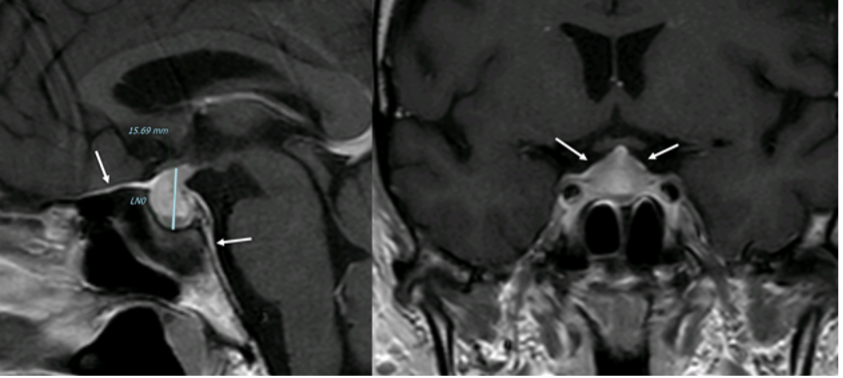

Figura 21

RM coronale T1 senza (a sinistra) e con Gd (a destra) in due diversi pazienti (sopra e sotto, grazie a Regina Barbò per questa immagine). Si evidenzia una massa intra-ipofisaria ben demarcata (freccia rossa), di diametro < 10 mm, ipointensa rispetto all'ipofisi normale. Dopo mdc l'impregnazione del microadenoma è meno rapida di quella dell'ipofisi normale circostante. Notare la deviazione controlaterale del peduncolo ipofisario nelle immagini in basso (freccia gialla)

Figura 21bis. RM, sequenze SE, immagini T1, sezioni coronali senza (A) e con mdc (B) e T2 (C). Microadenoma cistico: lesione espansiva del lobo destro dell’adeno-ipofisi, ovalare a contorni definiti, modicamente, uniformemente ipointensa in T1 basale e caratterizzata da franca ipointensità nell’immagine dopo somministrazione di mdc, che condiziona un fisiologico blush del parenchima ipofisario sano. La spiccata, omogenea iperintensità di segnale nell’immagine T2 conferma la struttura cistica dell’adenoma, del tutto verosimilmente secondaria a sanguinamento intra-lesionale (grazie a Regina Barbò)

Circa il 10-30% dei micro-adenomi (specie PRL) vengono individuati esclusivamente nelle sequenze post-contrastografiche e la tecnica dinamica incrementa la sensibilità di un ulteriore 10% (4).